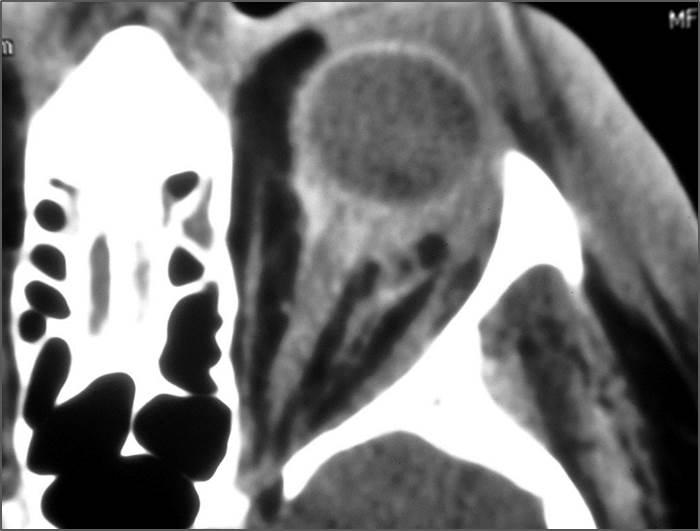

Eyes

Proptosis is present.

The optic nerve has a stretched appearance.

There are signs of a decompressed globe.

There is evident general optic sheath swelling or swelling at the junction of the globe and sheath to suggest an optic sheath hematoma.